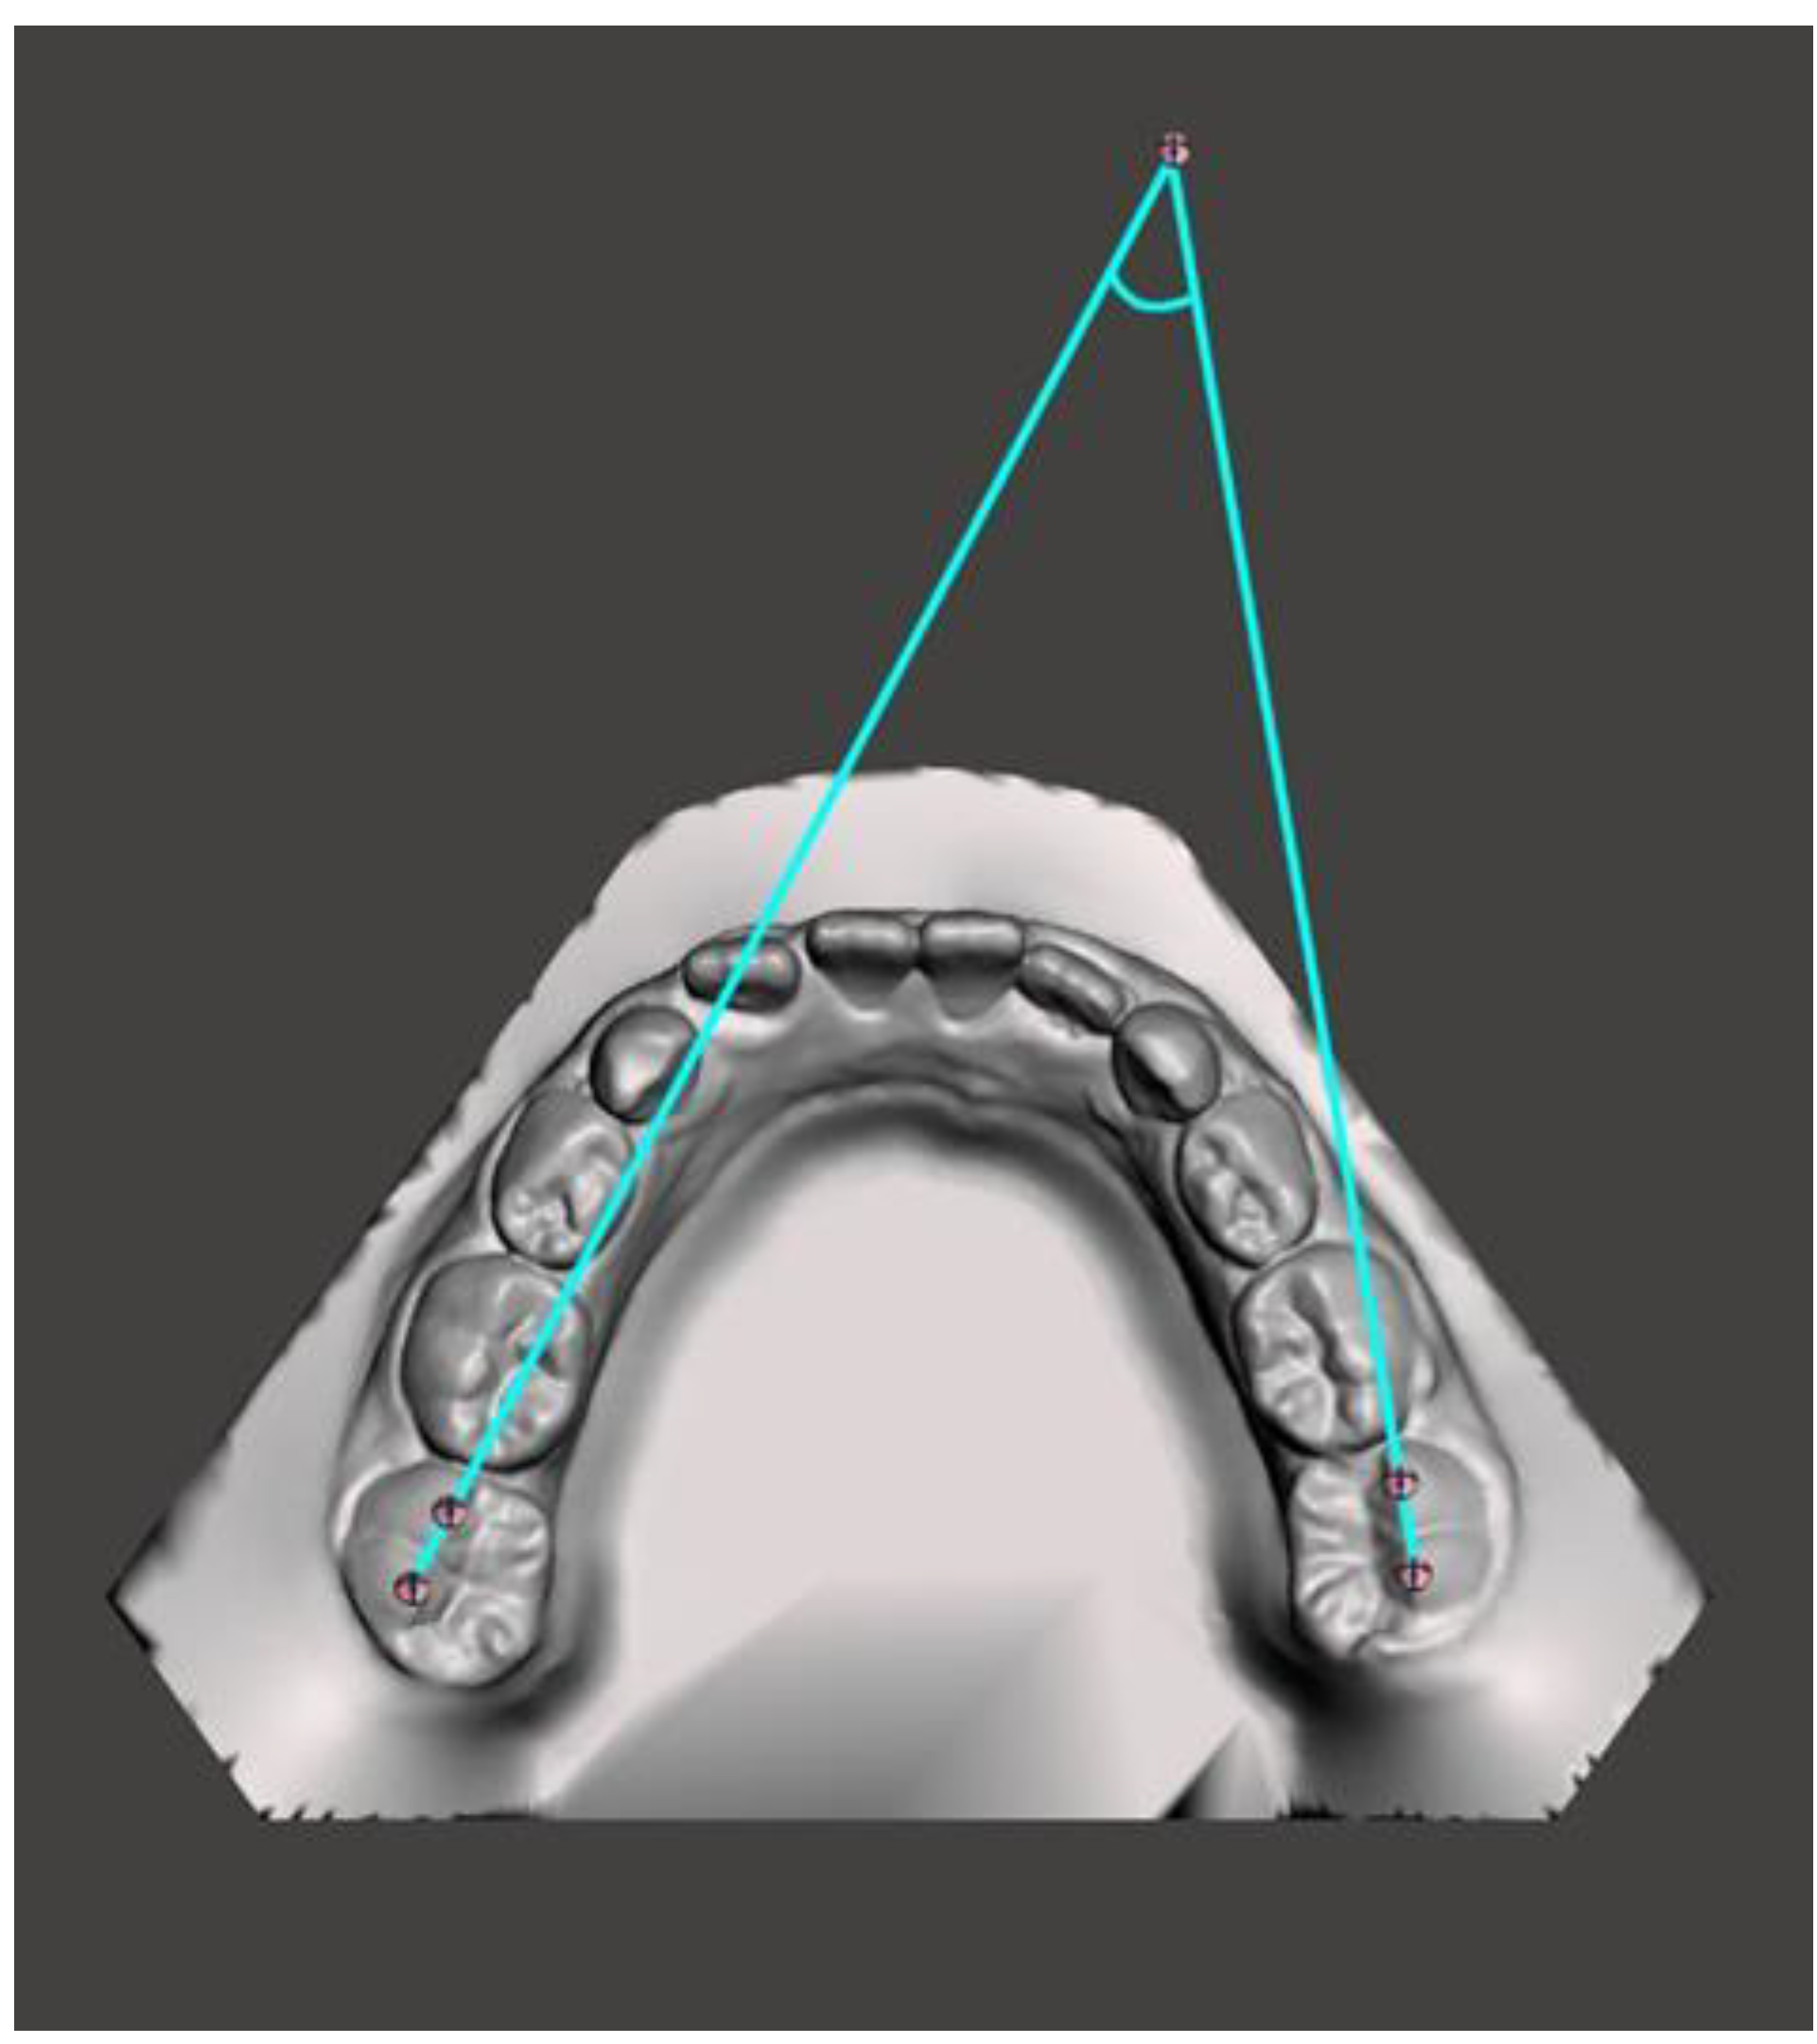

Figure 6.

Mandibular occlusal angle.